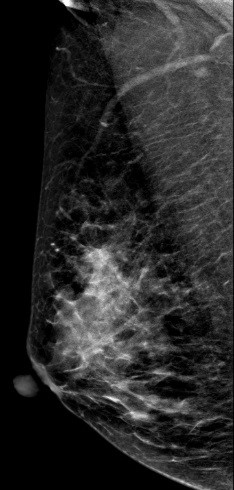

病史:患者43岁,发现右乳包块2周。

2D图像:

常规2D图像MLO位上象限见一团块状影,在CC位上并没有发现可疑异常密度影,在V-Preview图像和tomo图像上我们可以清楚发现病变边界不清见长短不一毛刺,呈星芒样改变。

右乳上方略偏外局限致密影BI-RADS 4B 。

在TOMO图像上对星芒样病灶周边情况显示明显优于2D图像,最后病理证实右乳浸润性导管癌。